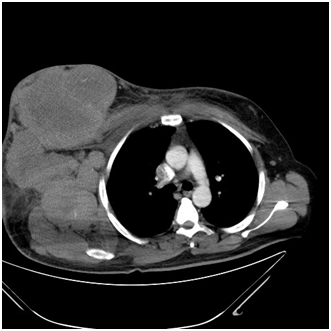

Figure 1 Contrast enhanced axial CT of the abdomen showing a pelvic and iliac fossa mass displacing the displacing the uterus with mesenteric and omental deposits.

Figure 10 Contrast enhanced axial CT sections of the thorax showing a heterogenous mass arising from the chest wall.

Figure 11 Contrast enhanced axial CT sections of the thorax showing a heterogenous mass arising from the chest wall with large axillary lymph nodes.